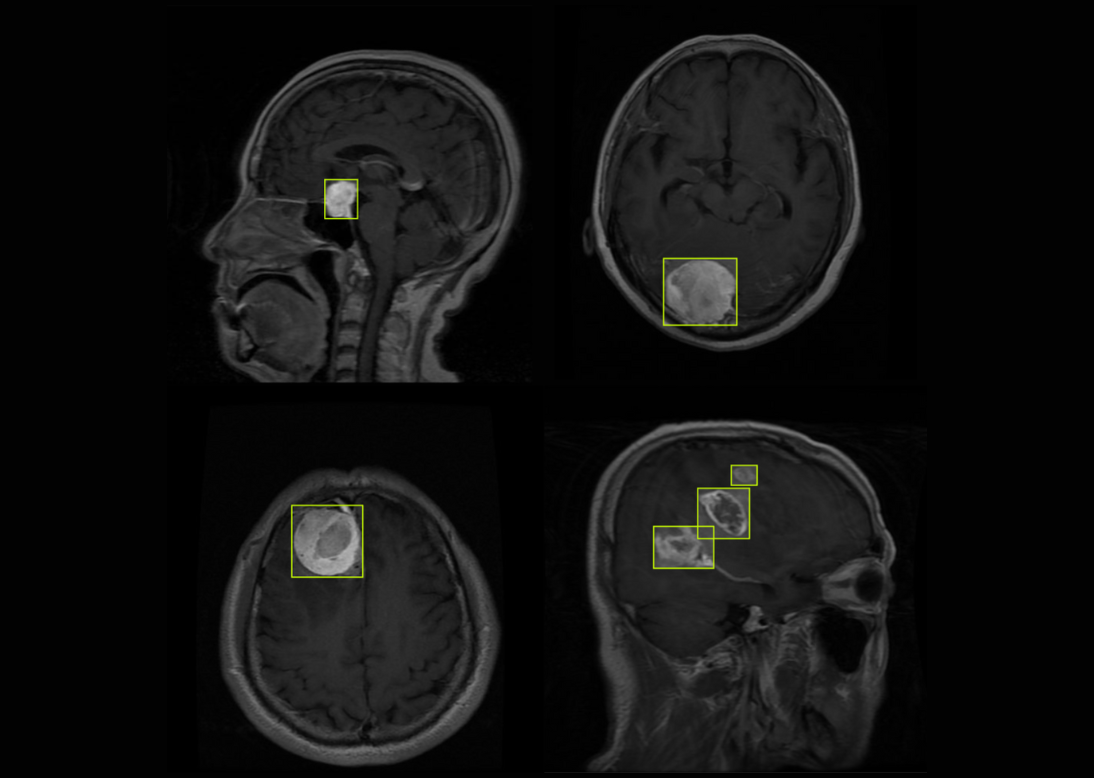

Expert radiology data annotation for diagnostic imaging datasets. We meticulously label anatomical structures and abnormalities across X-rays, CT scans, MRIs, and ultrasounds to train AI models that enhance diagnostic accuracy and support radiologists in clinical decision-making.

Advanced surgical video labeling for AI-assisted procedures. We annotate surgical instruments, anatomical landmarks, tissue types, and procedural steps in endoscopic and robotic surgery footage, helping develop intelligent systems that enhance surgical precision and safety.